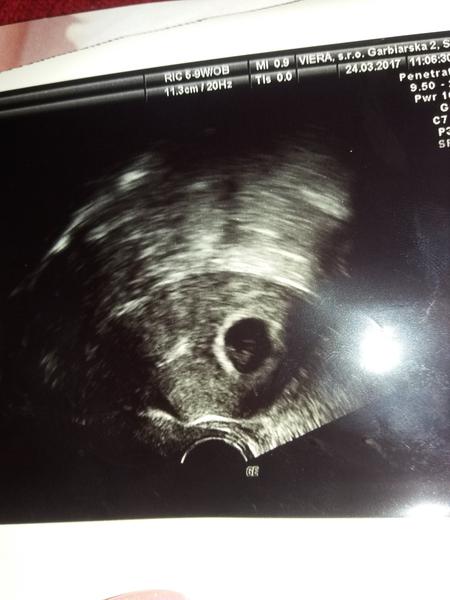

Tak zienky tu je moja fazulka 🙂 som v 7tt 🙂 doktorka povedala ze je vsetko v poriadku, cakala som ze mi da nejake lieky ako aj niektorym babam sem ale nedala mi nic. Len ze sa mam setrit nedvihat tazke... a dalsia kontrola bude 19.4 tak duufam ze bude vsetko v poriadku... 🙂 vypisala mi uz aj tehotensky preukaz 🙂